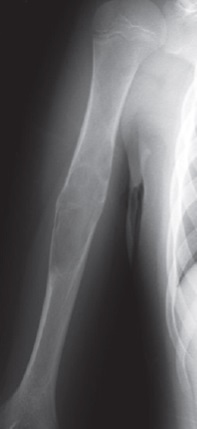

1

Q

Qual diagnóstico?

A

Lesão epifisária excêntrica

Fise aberta

dx: condroblastoma